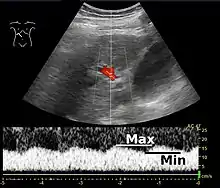

Portal vein pulsatility can be measured by Doppler ultrasonography. An increased pulsatility may be caused by cirrhosis, as well as increased right atrial pressure (which in turn may be caused by right heart failure or tricuspid regurgitation).[9] Portal vein pulsatility can be quantified by pulsatility indices (PI), where an index above a certain cutoff indicates pathology:

| Index | Calculation | Cutoff |

|---|---|---|

| Average-based | (Max - Min) / Average[9] | 0.5[9] |

| Max-based | (Max - Min) / Max[11] | 0.5[11][12] - 0.54[12] |